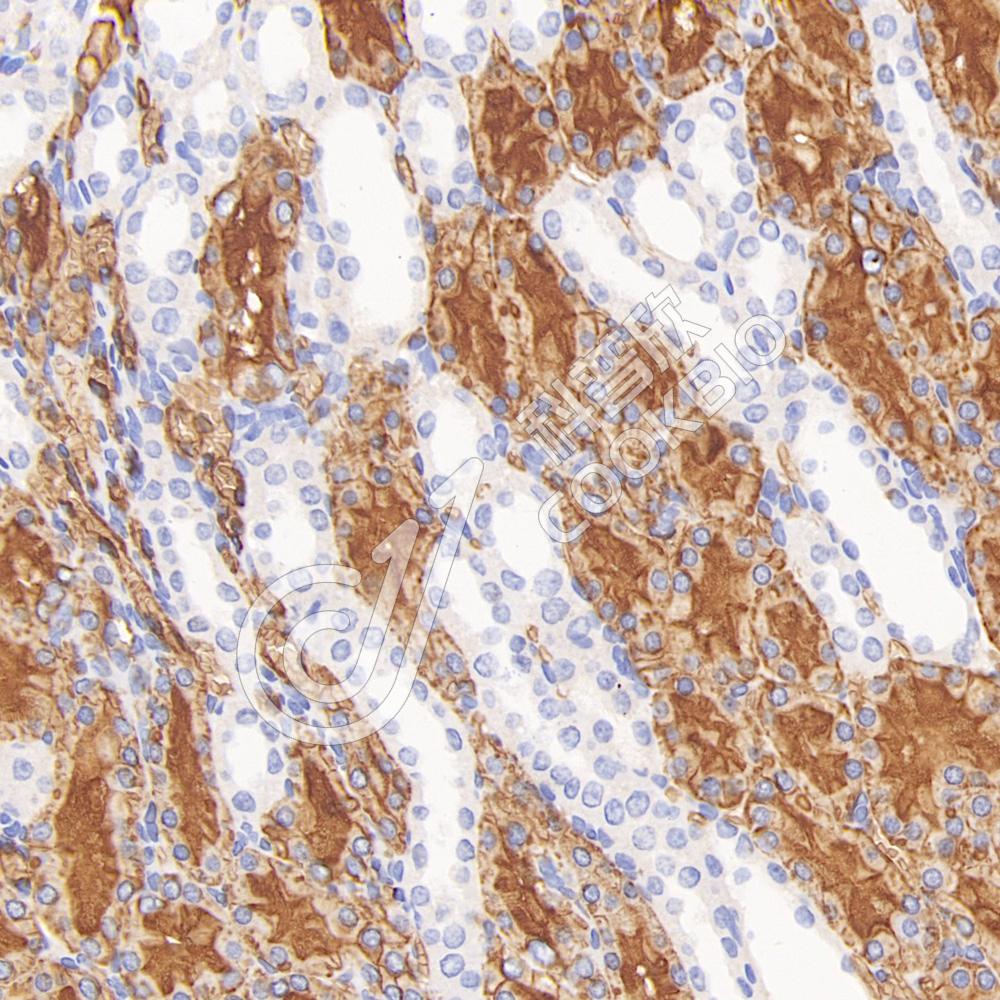

IF检测NMDAR1蛋白(货号 K133432)(红色).

样品: 大鼠脑, 4%多聚甲醛 (货号KSG1101) 固定12-24小时.

抗原修复: Tris-EDTA抗原修复液(pH 9.0) (KSG1203), 98℃, 20分钟.

封闭: 3% BSA(货号KSGC305010)的PBS溶液, 室温孵育30分钟.

—抗: 1: 300稀释, 4℃ 孵育过夜.

二抗: Cy3标记山羊抗兔IgG (H+L) (货号KB63909), 1: 300稀释, 室温孵育1小时.